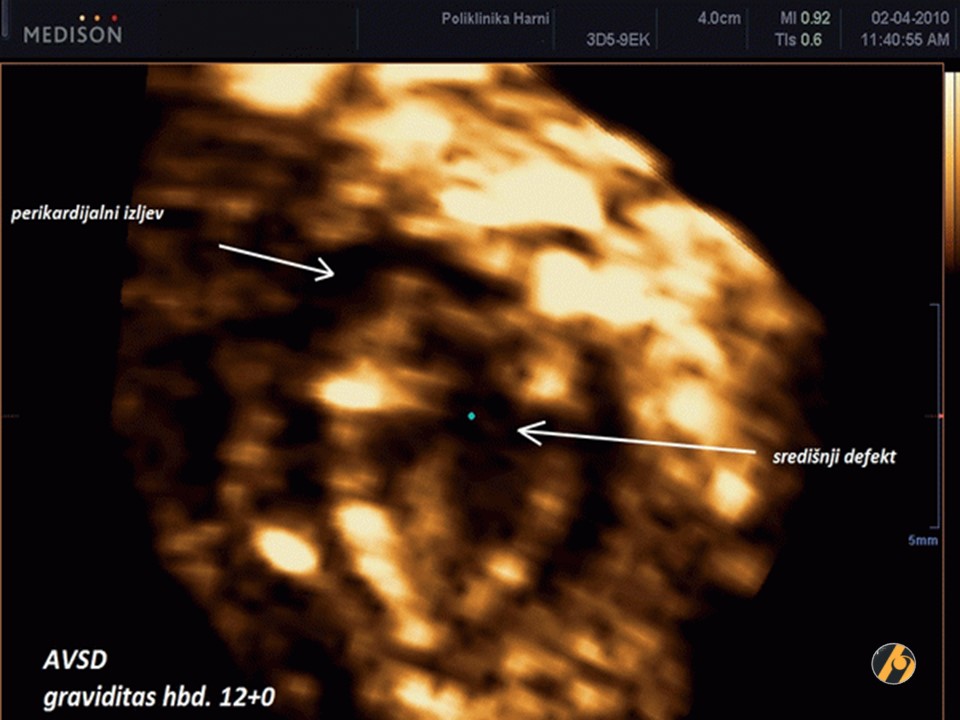

Anomalije srca i velikih arterija najčešće su prirođene anomalije s učestalošću kod rođenja od oko 8 na 1.000. Općenito, oko polovice istih je asimptomatska, a druga polovica klasificirana je kao velike anomalije jer su letalne te je potrebna operacija ili interventna kateterizacija srca tijekom prve godine života.

Velike srčane greške čine oko 20% svih mrtvorođenih i 30% svih neonatalnih smrti zbog prirođenih anomalija. Postoji velika povezanost između povećanog nuhalnog nabora i srčanih grešaka u kromosomski abnormalnim i euploidnim fetusima. Veliki nuhalni nabor nije ograničen na specifične srčane mane. U euploidnih fetusa učestalost srčanih grešaka se povećava s povećanjem nuhalnog nabora sa 3/1,000 (normalan nuhalni nabor) na 125/1,000 (nuhalni nabor 5,5 mm ili veći).

Nuhalni nabor iznad 3,5 mm se nalazi u oko 1% trudnoća. U tim slučajevima postoji visoki rizik za srčane greške, a posebnu pozornost treba posvetiti pregledu srca i velikih arterija, kako u vrijeme mjerenja NT, tako i kod naknadnih pregleda s 14-16 tjedana i 20-22 tjedna.

Rana fetalna ehokardiografija je tehnički puno teža u 12. nego u 20. tjednu trudnoće jer je srce mnogo manje, a fetus je obično pokretniji. Cilj je prikazati četiri komore, izlazišta arterija, duktus arteriozus i luk aorte. Upotreba color dopplera je nužna za potvrdu normalnog protoka u obje komore i za identifikaciju izlazišta arterija. Uspješnost pregleda ovisi o CRL fetusa i stručnosti ultrasoničara. Specijalistički pregled s 12 tjedana može umiriti većinu roditelja da nema većih srčanih greški. U slučajevima s većim greškama, rani ultrazvuk može dovesti ili do ispravne dijagnoze ili barem do sumnji, pa se provode daljnje pretrage.

Slika prikazuje striventrikularni septalni defekt u kombinaciji s omfalokelom i izrazito povećanim nuhalnim naborom u 12. tjednu trudnoće. Kariotipizacija: Trisomia 18.